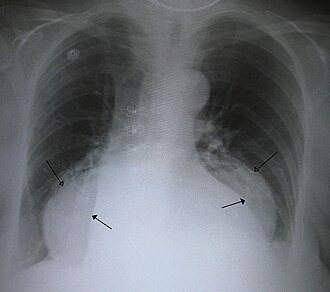

Dijagnosticira se gastroskopijom ili RTG pregledom želuca u Trendelembergovom položaju koji pokaže ulazi li želudac u grudni koš.